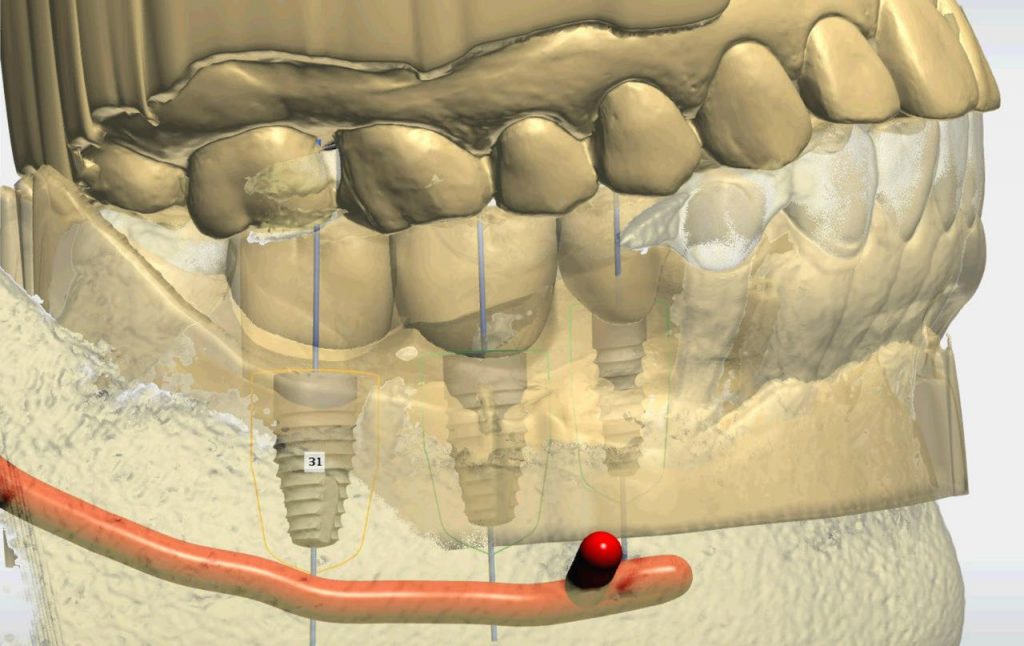

Digitally-Guided Dental Implants Placement with Osseodensification and Guided Bone Regeneration

Dr. H. Ryan Kazemi demonstrates the placement of three dental implants in sites #29, 30, and 31, using digital diagnostics and workflow, bone modification system, fully-guided implant placement and GBR technique for enhancement of the supporting bone and soft tissue.